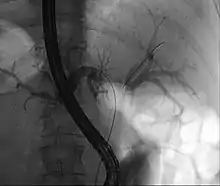

ERCP: stents placed in the left and right bile duct. At the right, the contrast that has been given before is already well-drained, making the bile ducts clearly recognizable.

Because of their location, these tumors tend to become symptomatic late in their development and therefore are not usually resectable at the time of presentation. Complete resection of the tumor, especially in early-stage disease, offers hope of long-term survival. However, patients that are candidates for resectability are few and moreover many of these patients will have a relapse despite apparent removal of the tumor. The type of surgery and the extent of the resection depend on the location of the tumor and the degree of extension.[16] In some cases, the obstruction, jaundice may present early and compel the patient to seek help. More often, liver resection is not a viable option because many patients are of advanced age, have multiple co-pathologies and are therefore at high risk.[17] Of late there has been renewed interest in liver transplantation from deceased donors along with add on therapy.[18] Prognosis remains poor.